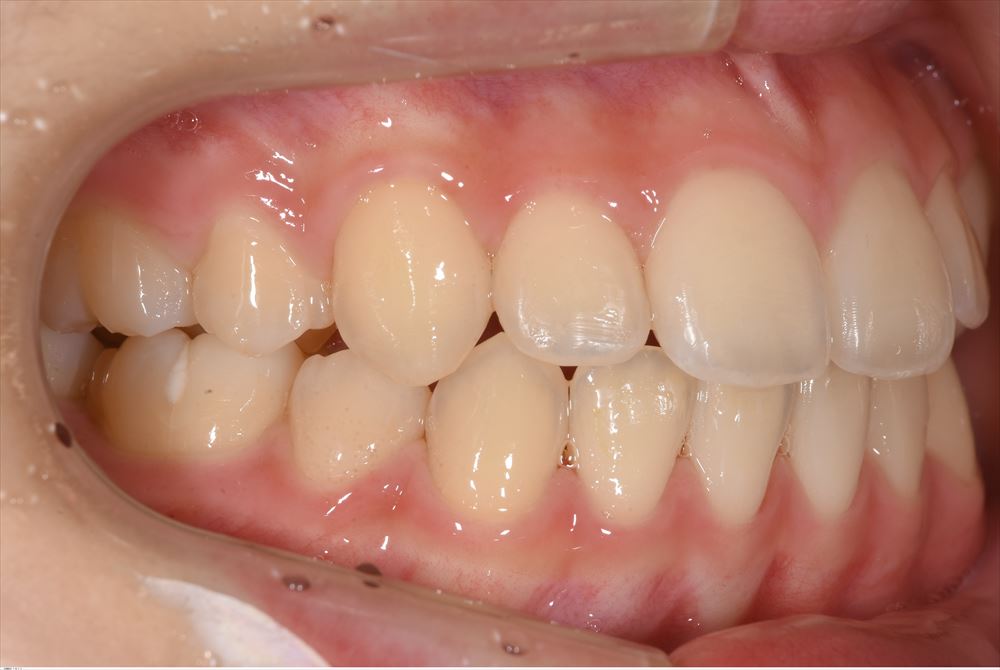

次のケースはハイブリットのセット

仮歯を外して

セット。喜んで頂けました。元々この方は中等度の歯周病でした。とても真面目に治療に参加して頂き歯周病の再発はありません。本当に感謝。次回PMTC!